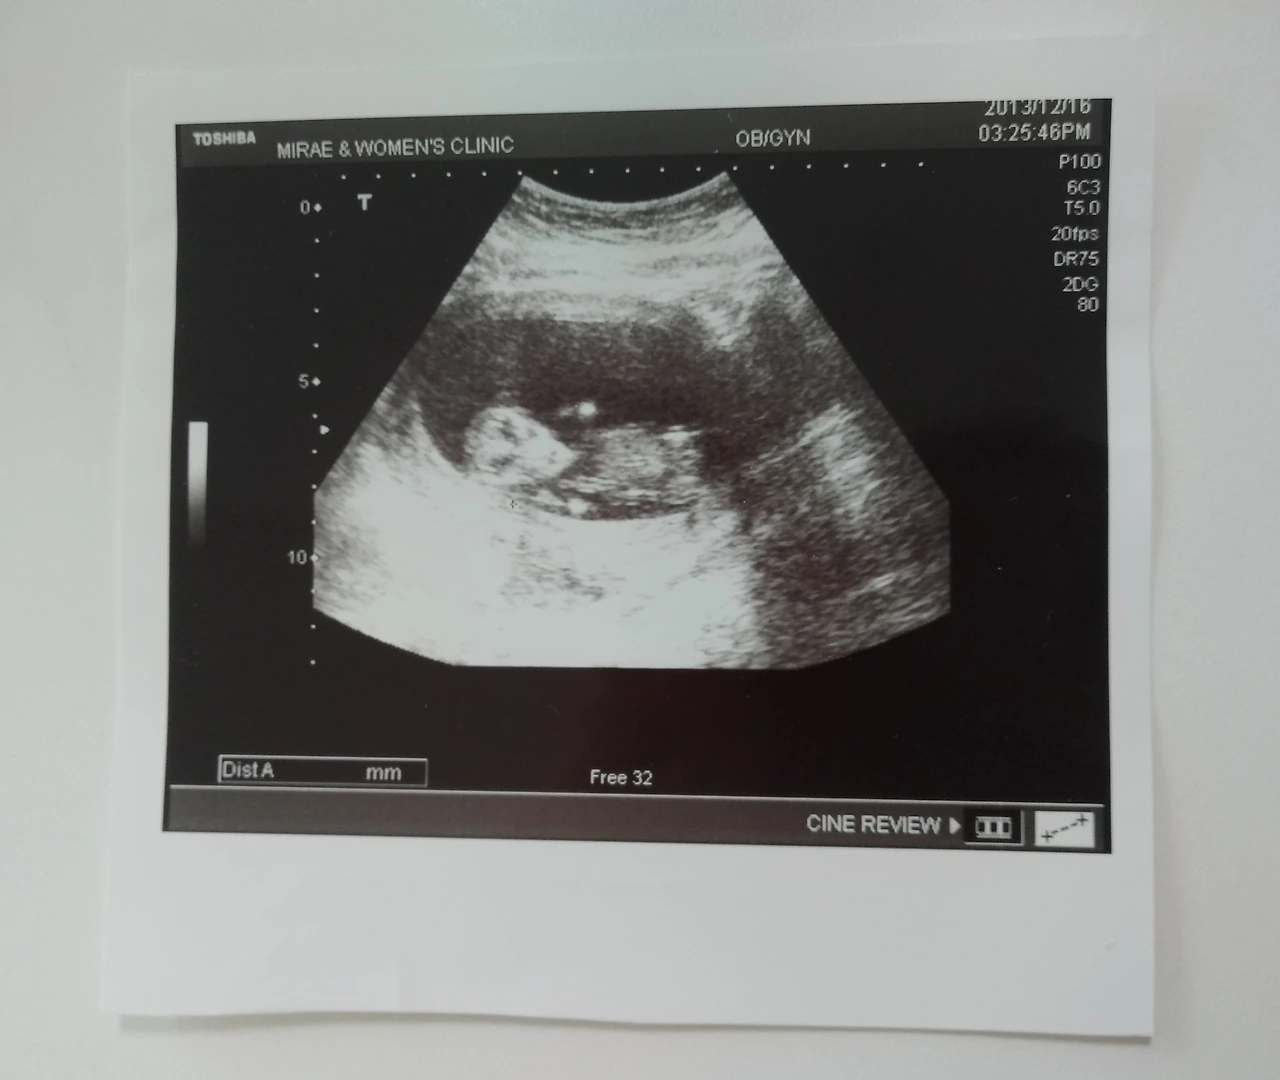

그리고 그렇게 아기를 보낸 지 석 달 만에 정말 고맙게도 우리의 바람처럼 아기가 건강해져서 다시 우리 부부에게 찾아왔습니다. 사실 처음 아가가 생겼을 때 태명이 미니미였기에 다시 찾아왔을 때도 우리 부부는 자연스레 미니미라 불렀습니다.^^

한 번의 아픈 경험이 있었기에 산모와 아기 둘 다 무척 건강하다는 얘길 들었음에도 불구하고, 그 어느 때 보다도 조심조심했습니다. 그리고 양가 가족들의 과잉보호(?) 속에서 지냈습니다.

그렇게 본의 아니게 양가 가족들의 가슴을 또 한 번 들었다 놨다 해버렸습니다. 다행히 큰 사고 속에서도 아기는 아무 일 없었던 듯 제 뱃속에서 신나게 놀고 있었습니다.^^

< 엄마~ 내 걱정 말아요~ 잘 놀고 있어요~ >